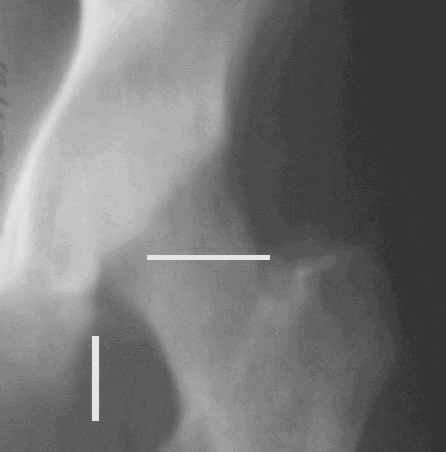

Уважаемые коллеги! Заканчивая обследование больного с переломо-вывихом бедра сделал ему обычные R-томограммы. Кажется удалось "поймать" и отломок и донорское место. Мои выводы - в скиаграмме. Считаю, что это передне-нижний фрагмент головки, образовавшийся вследствии отрывного перелома. На томограммах отломок обозначаю длинной стрелкой, а место откуда он оторвался - более короткой. Учитывая тот факт, что его размеры по КТ 25 х 15 мм считаю, что его фиксация на место необходима для профилактики артроза, что при 16-ти летнем возрасте пациента важно в плане максимального отодвигания эндопротезирования. Планирую оперировать его 24.05.05 г. Результаты представлю.

Прямой 19.05

Несколько соображений к "картинкам". На прямом снимке и КТ-томограммах все типичные линии вертлужной впадины: крыша, передняя стенка, задняя стенка - сохранены. На КТ-сканах 6 и 7 появляется фрагментация головки. С учетом R-томограмм отломок расположен спереди-снизу, а не сзади-сверху от сустава, как написано в описании КТ.